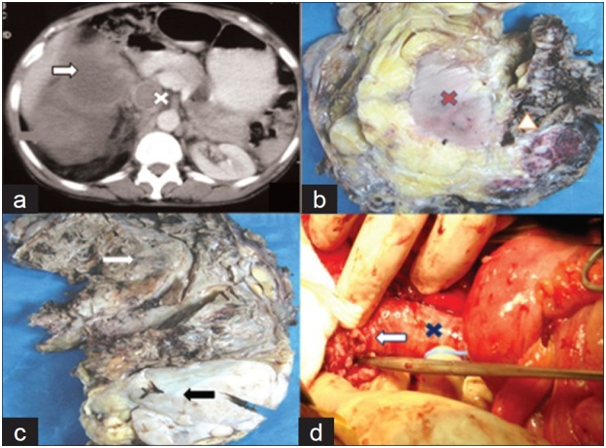

Shastri et al.5 reported a 65-year-old man who had presented with a lump in his abdomen and right flank pain of 4 months duration. He was asymptomatic otherwise. He did have a large, nodular mass was found in his right hypochondrium, epigastrium, and lumbar region. He radiology imaging studies including ultrasound with Doppler scan, computed tomography (CT) scan, and magnetic resonance imaging (MRI) scan which showed a mass within the upper pole and mid pole of the right kidney that measured 20 cm x 16 cm x 10 cm which had extended from the subdiaphragmatic region to the bifurcation of the aorta. Additionally the radiology images had also shown retroperitoneal lymph node enlargement and thrombus within the intravenous vena cava (IVC) with some doubtful fat density (Figure 1A). Thrombus was seen within the inferior vena cava which had extended from the intra-hepatic part of the IVC to the right common iliac vein. Based upon the radiology image findings a provisional clinical diagnosis of right renal cell carcinoma was made. During operation the tumour was found to have extended from just inferior to the liver down to the bifurcation of the aorta. The tumour was adherent to the wall of the IVC at the confluence of the right renal vein and the IVC and in view of this about 2 cm patch of IVC was resected and the IVC repaired (Figure 1D). The man therefore underwent right radical nephrectomy and removal of all the thrombus within the IVC. Gross examination of the specimen showed on cut surface, a large heterogeneous growth which had consisted of a distinct large necrotic tan brown area together with smaller fleshy yellowish part which together had measured 20cm x 14cm x 9m see Figure 1C and this was found to have infiltrated the renal sinus and had encased the rest of the kidney completely (Figure 1B). The macroscopically normal looking kidney did measure 11cm x 6cm and it could be easily shelled out from the tumour mass with the exception of the renal sinus, which in the opinion of the surgeon had suggested a possible origin of the tumour from the renal sinus. Microscopy examination of sections of the necrotic tan brown area showed a malignant mesenchymal tumour which was predominantly malignant fibrous histiocytoma (MFH)- like high grade sarcoma with brisk mitosis of between 20 to 25 mitoses per 10 high power field (Figure 2A). Microscopy examination of the tumour within the white fleshy area did reveal a well-differentiated liposarcoma that showed lipoblasts that had been lying within myxoid and focally sclerosed background, which had been well demarcated from the de-differentiated part (Figure 2B). The tumour was noted not to have infiltrated the kidney in any part of the planes with the exception of the renal sinus (Figure 2C). Microscopy examination of sections of tumour thrombus from the IVC did reveal de-differentiated areas of tumour only (Figures 2E & 2F). There was no evidence of tumour at the surgical resection margins including the ureter and renal artery. Based upon the overall microscopy features of the tumour a diagnosis of de-differentiated liposarcoma was made. Immunohistochemistry studies of the tumour showed that they tumour cells had exhibited strongly positive staining for vimentin and S-100 but negative staining for pancytokeratin, epithelial membrane antigen (EMA), desmin, and KMB-45 (Figure 2D). He received 6 cycles of combination chemotherapy which included doxorubicin and ifosfamide and he had n uneventful follow-up for 9 months at the time of the publication of the case report. Shastri et al.5 iterated that their case was the first case of liposarcoma of the kidney with tumour thrombus within the IVC that had been successfully treated by means of nephrectomy and post-operative chemotherapy with an ensuing uneventful follow-up.

• Figure 1 (A) Pre-op CT scan showing large heterogeneous mass in renal area with large non-fatty dedifferentiated area (white arrow) and smaller hyper-intense fatty area (red arrow) along with IVC thrombus with largely nonfatty area (cross); (B) Kidney (marked by cross) was encased by the tumour and could be easily shelled out from mass except at renal sinus (arrow head); (C) Mass comprised of large necrotic tan brown area (white arrow) with smaller fleshy white area (black arrow); (D) Intra-operative removal of tumour thrombus (cross) at renal outlet (arrow): Reproduced from:5 Shastri C, Kumar J, Jaiswal S, Mandhani A. Renal differentiated liposarcoma with intra-caval tumor thrombus: A rare case. Indian J urol. 2012 Apr-Jun; 28(2): 208 – 210. under copyright © Indian Journal of Urology This is an open-access article distributed under the terms of the Creative Commons Attribution-Noncommercial-Share Alike 3.0 Unported, which permits unrestricted use, distribution, and reproduction in any medium, provided the original work is properly cited. For commercial use copy right permission must be obtained from the original source.